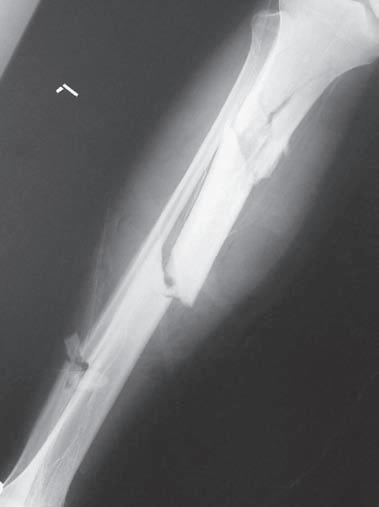

Obr. 2.3 Tříštivá zlomenina diafýzy tibie – hlavní fragmenty, tj. proximální a distální, nejsou v kontaktu. Typ C podle AO klasifikace

C – tříštivé – hlavní fragmenty nejsou v kontaktu ani po repozici (obr. 2.3).